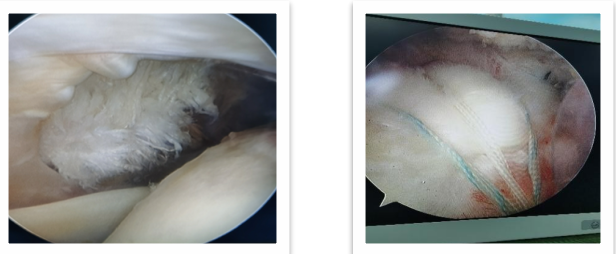

没错,他们都需要用到——肩关节镜别看这小小的镜子,它在关节与运动医学中却有着大大的用处。前文提到的几名患者都是采用微创肩关节镜手术方式解决他们烦扰的病痛的,并得到极好的疗效。

很多人觉得做手术是件很可怕的事,但肩关节镜其实是一种微创手术,它是通过2-3个不到0.5cm的小切口来诊断和治疗肩关节疾病,损伤很小,恢复快。其目的是让原本疼痛的肩关节术后不再疼痛,原本存在胳膊抬不起来的情况做完能抬起来,原本反复脱位做完后不再脱位了,从而提高患者的生活质量。

3、肩关节不稳:盂唇损伤修复术

4、肩袖撕裂:肩袖修补术